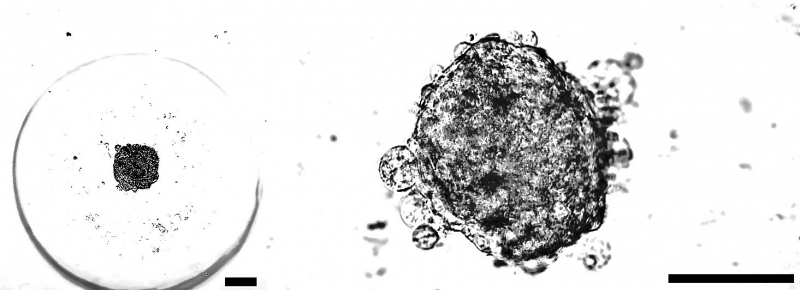

Как отмечают ученые, подобные технологии развиваются во всем мире, однако новаторство представленной разработки — в способе «сбора» стволовых клеток. Их выращивают в виде сфероидов — клеточных комплексов в виде сферы размером от 100 до 200 нанометров. Такая форма позволяет клеткам развиваться в среде привычных им взаимосвязей, что повышает их выживаемость после введения в организм. Поэтому сфероиды показывают большую эффективность по сравнению с единичными клетками.